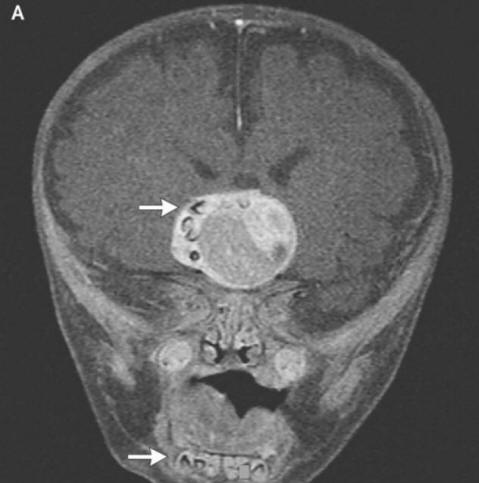

Chirurgové z amerického státu Maryland museli jeden utratit nejtěžších operací ve své praxi. Čtyřměsíční rodiče chlapci vydali poplach a poté šli k doktorům všimli si, že hlava jejich dítěte roste příliš rychle. Lékaři provedl sken a zjistil, že v mozku pacienta vyrostl zub.

Foto z otevřených zdrojů Jak chirurgové vysvětlili vystrašeným rodičům a onkologové to bylo způsobeno tvorbou vzácného vrozeného tumory – kraniofaryngiomy, píše New England Journal of Medicine. Tento novotvar ve velké většině případů benigní však může růst na velikost míče golf a způsobuje pokles čichu, zhoršeného sluchu a zraku, a také zvyšuje intrakraniální tlak. Výzkumníci vždy podezření, že tyto nádory, které se objevují u dítěte již v r těhotenství, vytvořené ze stejných buněk jako zuby, protože zjistili velké hromadění vápníku, ale skutečně vytvořený zub před tímto případem, který nemohou najít započítal.

Chirurgové úspěšně odstranili fotografii z otevřených zdrojů The tumor, chlapec, říkali, si vede dobře. To je ale zub vyrostl ve své hypofýze, ale narušil mozek, zejména, správná produkce hormonů – pacient je bude muset vzít dříve konec života. Tento případ se může právem pyšnit místem seznam nejpodivnějších operací prováděných onkology. Mezitím v roce mladý muž z Íránu, který musel léčit chlupaté oči. Téměř se mu objevil podivný nádor v jeho oku ihned po narození, ale ve věku 19 let se výrazně zvýšila v roce 2005 o velikosti (do 0,6 cm) a zabránila tomu, aby byla víčka navíc uzavřena ztuhlé vlasy začaly růst. Lékaři odstranili nádor a zjistili, že toto je limbální dermoid – obvykle velmi vzácný benigní vzdělání. Podle lékařů v tom případě pokud mladý muž pokračoval v tažení léky, jeho otok mohl nejen pěstovat vlasy, ale také se začal potit: postupem času u novotvarů se často objevují odpovídající žlázy.